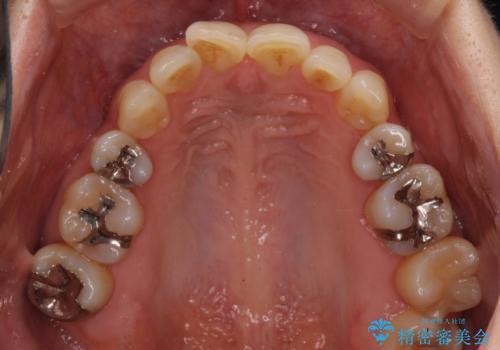

矯正治療後には、下顎臼歯の目立つ銀歯をセラミックインレーにて修復治療を行いました。

口を開けたときに金属が見えなくなり、患者様には大変満足していただきました。